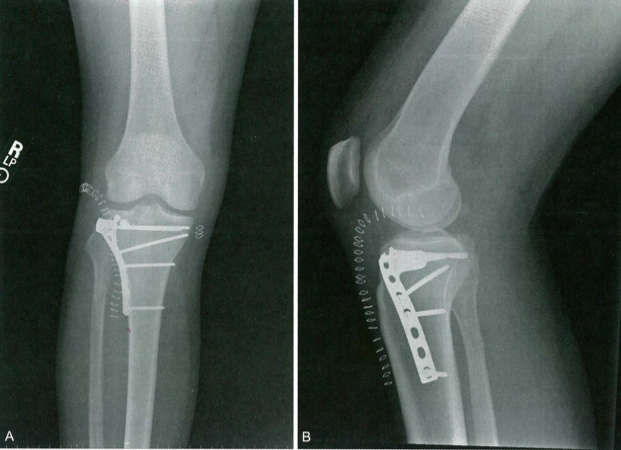

Классификация переломов плато большеберцовой кости по Шацкеру и Холь-Муру

Переломы плато большеберцовой кости являются результатом сильного вальгусного напряжения в сочетании с осевой нагруз···